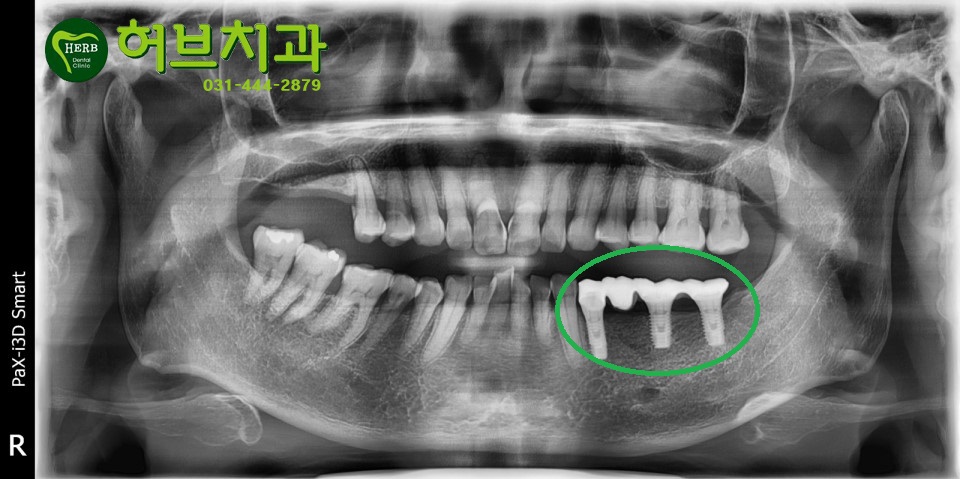

이경우 네개의 치아가 빠지셨지만 여자분이시고 작은어금니는 한개만 있어도

씹는 힘을 충분히 버티니 네개 부위에 세개만 심고 브릿지로 제작해드렸습니다.

뼈상태가 좋으셨고 환자분도 술담배를 안하시는 관계로

2개월 반만에 바로 치아 모양으로 만들어

지금은 식사를 잘하고 계십니다.